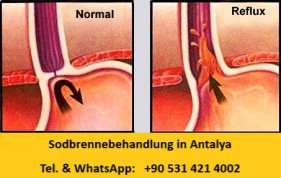

Sodbrennenbehandlung / Refluxoperation, Antalya,Türkei

Deutsch sprechender Arzt, Adipositas Zentrum Antalya Türkei

Die Sodbrennoperation wird vom deutsch sprachigen Arzt, im Adipositaszentrum in

Antalya laparoskopisch durchgeführt.

Kosten, Preise Sodbrennoperation Antalya, Türkei.

Eine Sodbrennen Behandlung / Reflux-Operation kommt vor allem bei extrem starkem Sodbrennen, das den Betroffenen

schon über einen langen Zeitraum plagt &

auf keinerlei Behandlungsmethoden anspricht, zum Einsatz. Sie kann den Erkrankten nicht nur von seinen Beschwerden befreien, sondern auch den damit verbundenen psychischen Belastungen ein

Ende bereiten.

Der Alltag scheint dann häufig wie ein unüberwindbares Hindernis und auch die psychische Verfassung ist oftmals beeinträchtigt. Eine Reflux-OP kann diesen Betroffenen ein Stück Lebensqualität wiedergeben.

Was passiert bei einer Reflux-OP?

Oberstes Ziel der Reflux-OP ist es, den Weg der Magensäure vom Magen in die Speiseröhre zu unterbinden. Dieses Bestreben richtet sich nicht nur gegen die akuten Symptome, die ein nicht behandelbarer Reflux mit sich bringt, sondern vor allem auch gegen seine langfristigen Folgen.

Damit genau das nicht passiert, haben Ärzte die Antirefluxplastik, also Operationstechniken gegen auftretenden Reflux, entwickelt. So ist gewährleistet, dass aufgenommene Nahrung wie gewohnt die Speiseröhre passieren kann, um dann im Verdauungstrakt zerkleinert und verwertet zu werden. Füllt der Speisebrei den oberen Teil des Magens, dehnt sich dieser Bereich jedoch aus und verengt somit den Übergang von der Speiseröhre in den Magen. Der Effekt: Ein Zurückfließen des Mageninhalts ist damit kaum noch möglich.

Die meisten Patienten leiden danach nicht mehr oder kaum noch an lästigem Sodbrennen.